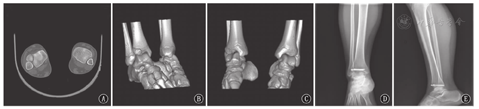

术后复查X线片或CT确定骺板和关节面达到解剖复位,短腿石膏固定4~6周。在石膏固定期间禁止患肢负重。4~6周摄片及临床检查均证实骨折坚强愈合后再让患儿开始进行功能锻炼(图1、图2)。

注:A~C:术前;D~E:术后6周

A-C:preoperative;D-E:6 weeks after operation